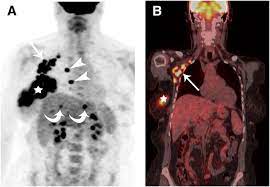

An mri scan of the breast may be. If you have a pet scan: Pet/ct scan combinations detect cancer in its earliest stages, when changes are happening at the cellular level. This combination scan is called a pet/ct. A ct scan of the heart may be ordered when various types of heart disease or abnormalities are suspected. In some cases, physicians use all three imaging techniques. This test may reveal whether breast cancer has spread to the bone. For example, ct has become a useful screening tool for detecting possible tumors or lesions within the abdomen. Learn how this test works, as well as its benefits and risks. It takes pictures from different angles. Why aren't pancreatic ct scans used in routine physical examinations to detect and prevent the spread of pancreatic cancer? A ct scan may be used to look for tumors in organs outside of the breast similar to a ct scan, a pet scan is a way to create pictures of organs and tissues inside the body. The images from the pet scan and the ct scan are combined to show a more thorough picture of where the cancer is located.

Breast Pet Scans from www.aboutcancer.com This allows detecting even minor changes, fixing the initial stages of tumor development and determining. Can a full body ct scan detect cancer? Mammogram and breast us may sometimes be better. Why aren't pancreatic ct scans used in routine physical examinations to detect and prevent the spread of pancreatic cancer? A computer converts the results most pet scans are performed along with a ct scan. Small as 1 mm in diameter, produces many false. It takes dozens of pictures of your lungs and chest and compiles the information together. If you have a pet scan:

Can Pet Ct Replace Separate Diagnostic Ct For Cancer Imaging Optimizing Ct Protocols For Imaging Cancers Of The Chest And Abdomen Journal Of Nuclear Medicine from jnm.snmjournals.org If you have a pet scan: Bone scans, positron emission tomography (pet), and computed tomography (ct) all continue to be employed alone or in combination for the detection of breast cancers suspected to have spread. Doctors use this type of mammogram in women with breast cancer, but with. Computed tomography (ct or cat) scan. Each has its own strengths. The ct can detect some masses that would then need further evaluation. An mri scan of the breast may be. This lung cancer awareness month learn how future processing is able to detect lung cancer from ct scans with the help of ai.